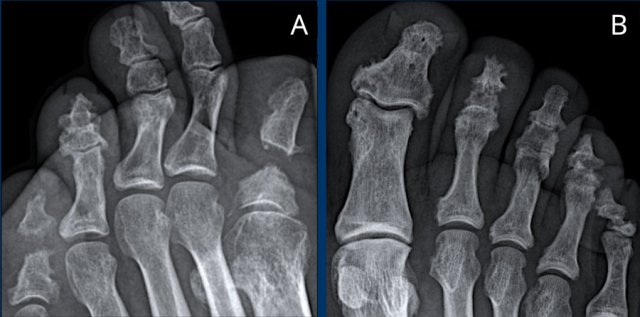

These radiographs are of two different patients with diabetes and neuropathic arthropathy.

A. Destruction of the tarsometatarsal joints with periarticular lucencies.

B. Typical radiological changes in the foot of a diabetic patient. There is lateral subluxation of the TMT joints (Lisfranc dislocation).

The changes in bone and joints itself may mimic severe osteoarthritis, severe inflammation or septic arthritis.

The key in this case is the clinical history with the presence of diabetic neuropathy.